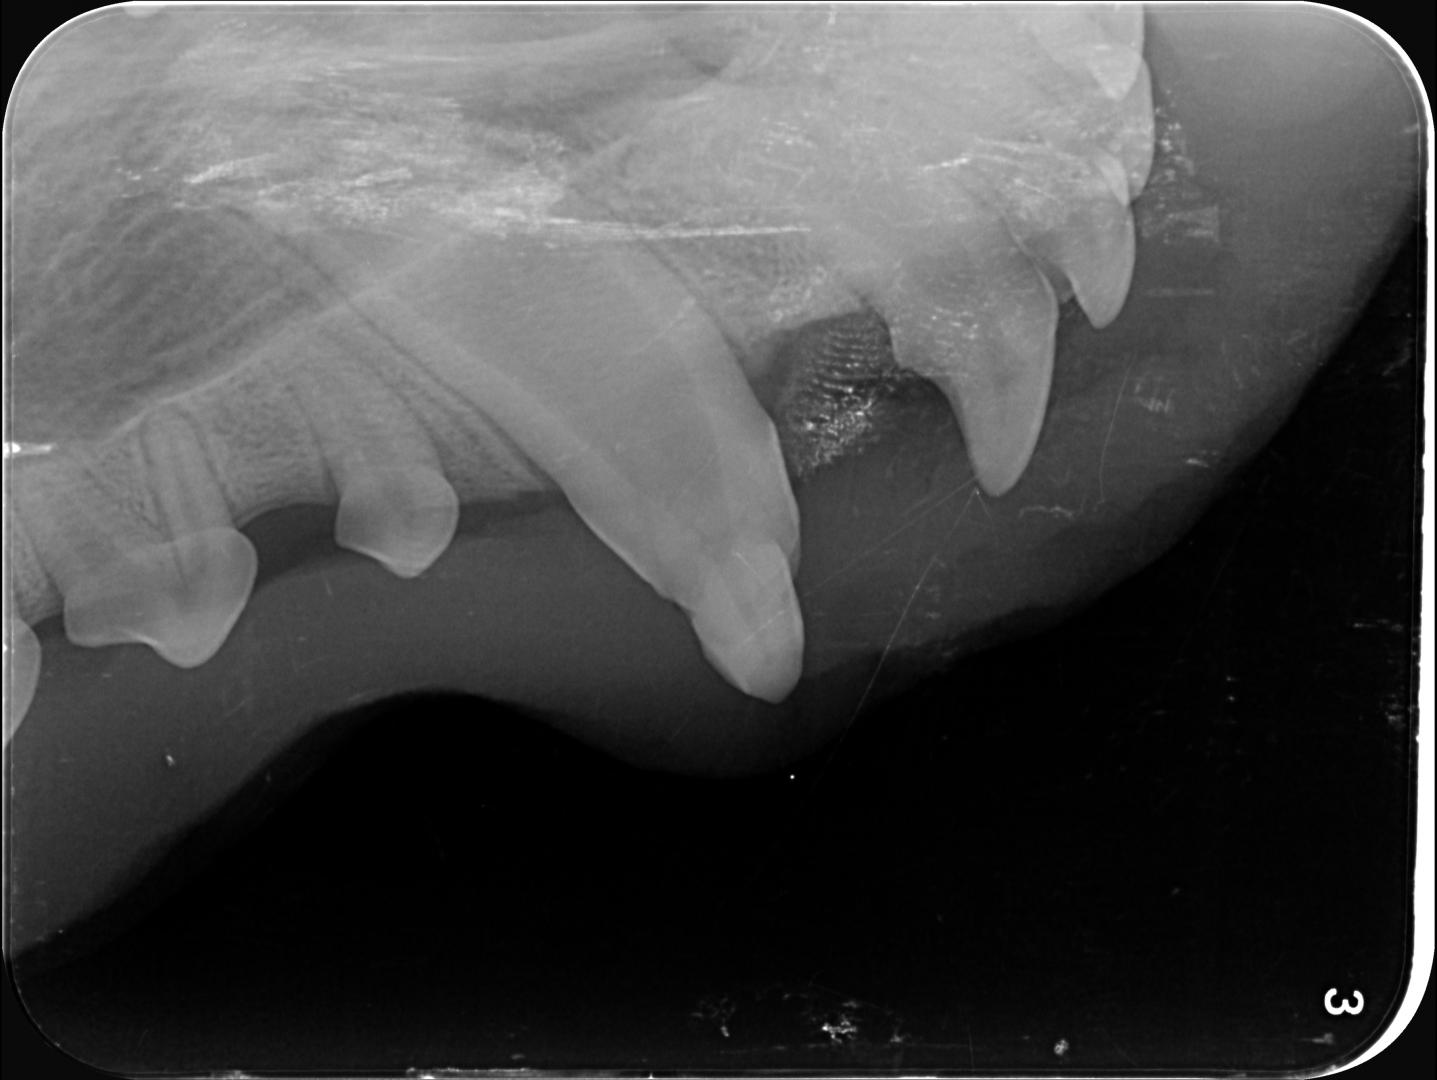

La décision est donc prise de tenter de la conserver, et de protéger la pulpe en déposant une couche de résine pour combler les surfaces abîmées du croc.

...et voilà le travail....!

Des trous comblés, une dent lissée, pour une fonctionnalité restaurée et une dent qui peut continuer à évoluer!

Des contrôles seront effectués pour s'assurer que la dent continue à évoluer normalement, et que la résine tient (avec un chiot qui a une forte tendance à mâchouiller tout ce qui lui passe entre les dents, rien n'est garanti!) l'objectif étant de permettre à Alphonse de conserver son beau sourire, et un croc fonctionnel!